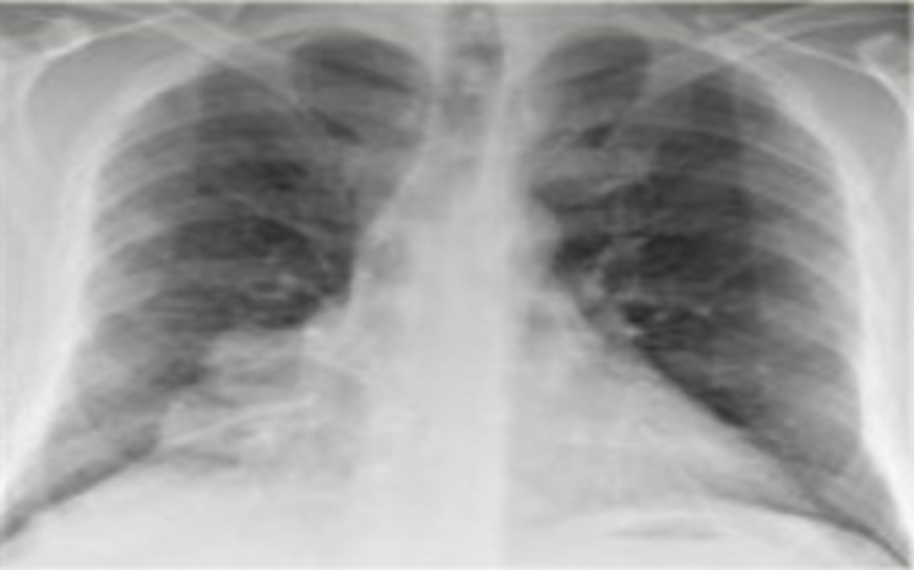

1-U thùy giữa phổi(P)